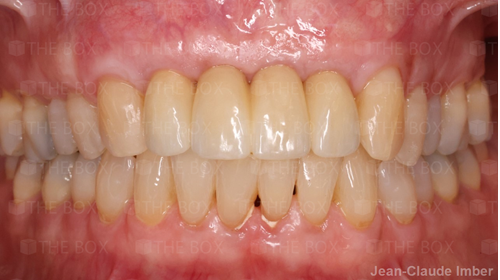

A new case was made public by Jean-Claude Imber check it out here.